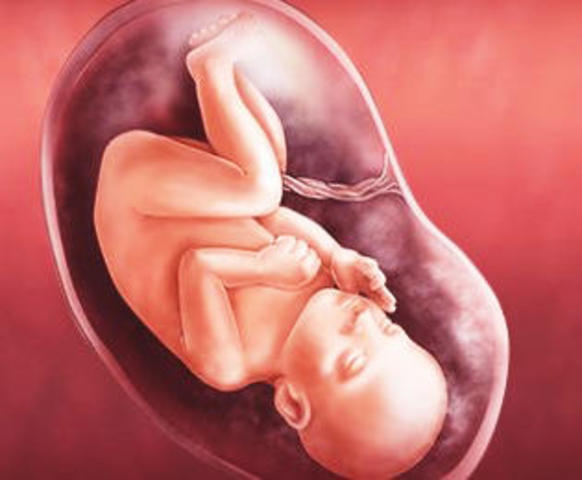

• 28 Semanas (Inicio tercer trimestre)

28 Semanas (Inicio tercer trimestre)

*La corteza cerebral ha madurado como para guardar conocimiento.

*Esta familiarizado con la voz de la madre.

*Adopta posición de preparación para el día del parto.